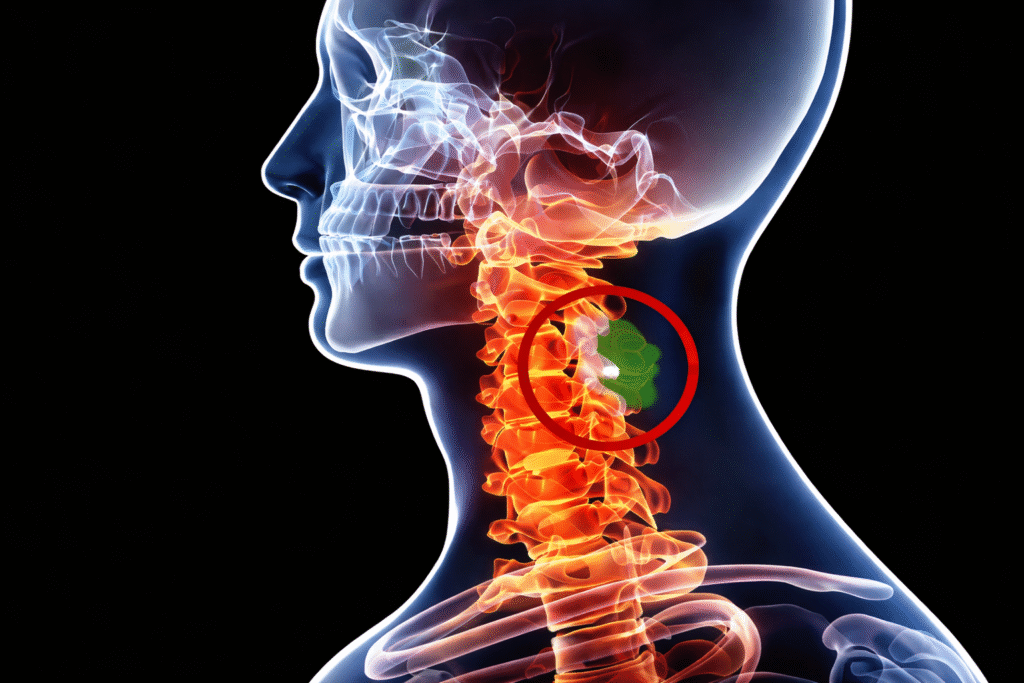

Cervical Disc

Herniation

Neck · Arm pain · Numbness

02 / 08→

Cervical

Stenosis

Neck narrowing · Cord pressure

- Neck: cervical disc herniation, cervical stenosis, cervical myelopathy, cervical radiculopathy.